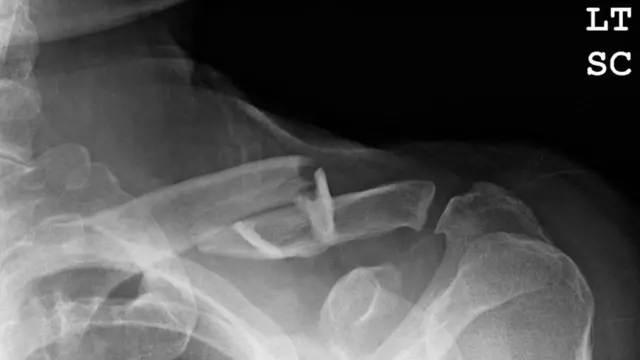

Sumber gambar, BSIP/UIG via Getty Images

Teriakan kesakitan, nyeri yang menusuk? Tidak selalu. Jika bisa digerakan artinya tidak patah? Belum tentu. Di sini Claudia Hammond menjawab sejumlah mitos tentang patah tulang.

Jika Anda bisa menggerakannya, berarti tidak patah!

Ini adalah hal pertama yang biasanya orang tanyakan ketika Anda kesakitan setelah jari kaki terantuk sangat sangat keras dan curiga kalau tulangnya patah. "Bisakah Anda menggerakannya? Jika ya, berarti tidak patah."

Bahkan, Anda kadang bisa membuat tulang patah bergerak, jadi itu bukan tanda utama yang harus dilihat untuk mencari tahu apakah tulang Anda retak.

Tiga tanda awal yang harus dilihat adalah bengkak dan bentuk yang tak wajar. Jika tulang keluar 90 derajat atau terasa menonjol di kulit, tidak mengejutkan, itu bukan pertanda baik dan mungkin tulang itu patah. Tanda lain adalah jika Anda mendengar bunyi 'tak' ketika insiden terjadi.